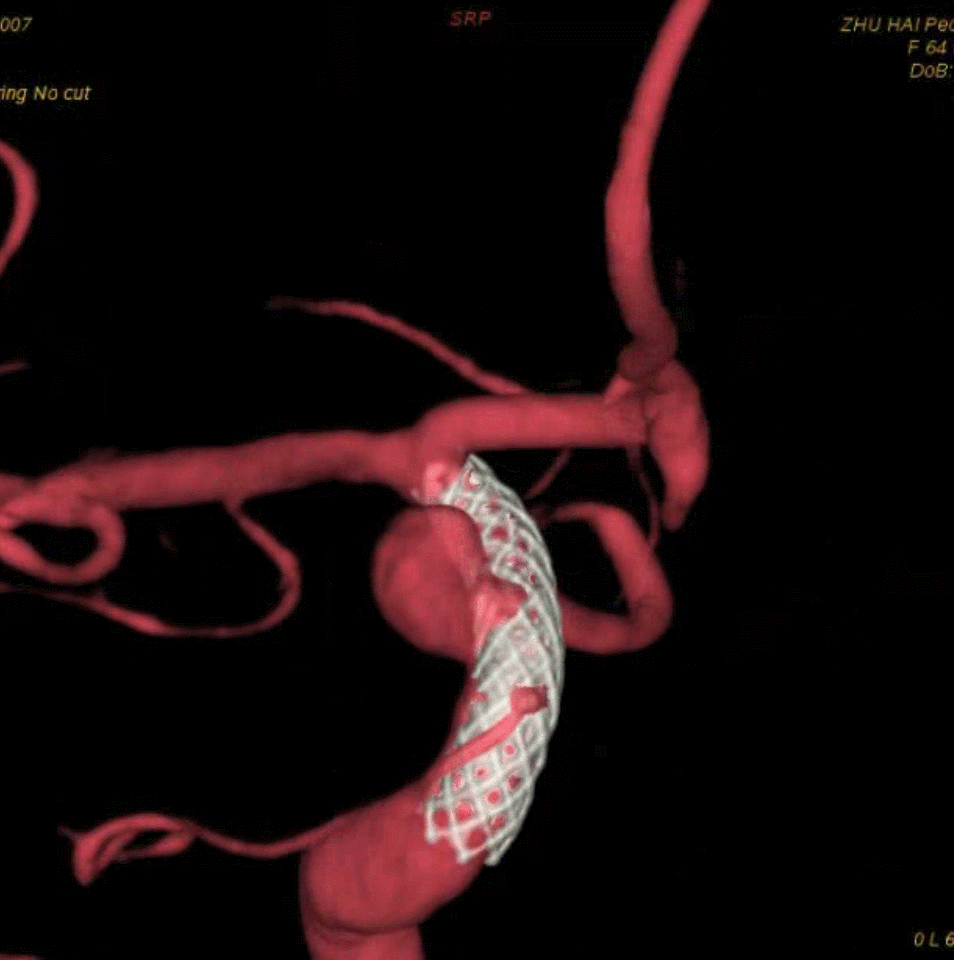

左侧瘤体形态欠规则,4mm×30mm Streamline 优先处理左侧动脉瘤

术后3月复查,瘤体未见显影,载瘤动脉通畅

同期4mm×20mm Streamline 进一步处理右侧动脉瘤

4mm×30mm Streamline

术后4月余随访:多发动脉瘤均未见显影,远端残余轻度狭窄

术前术后对比